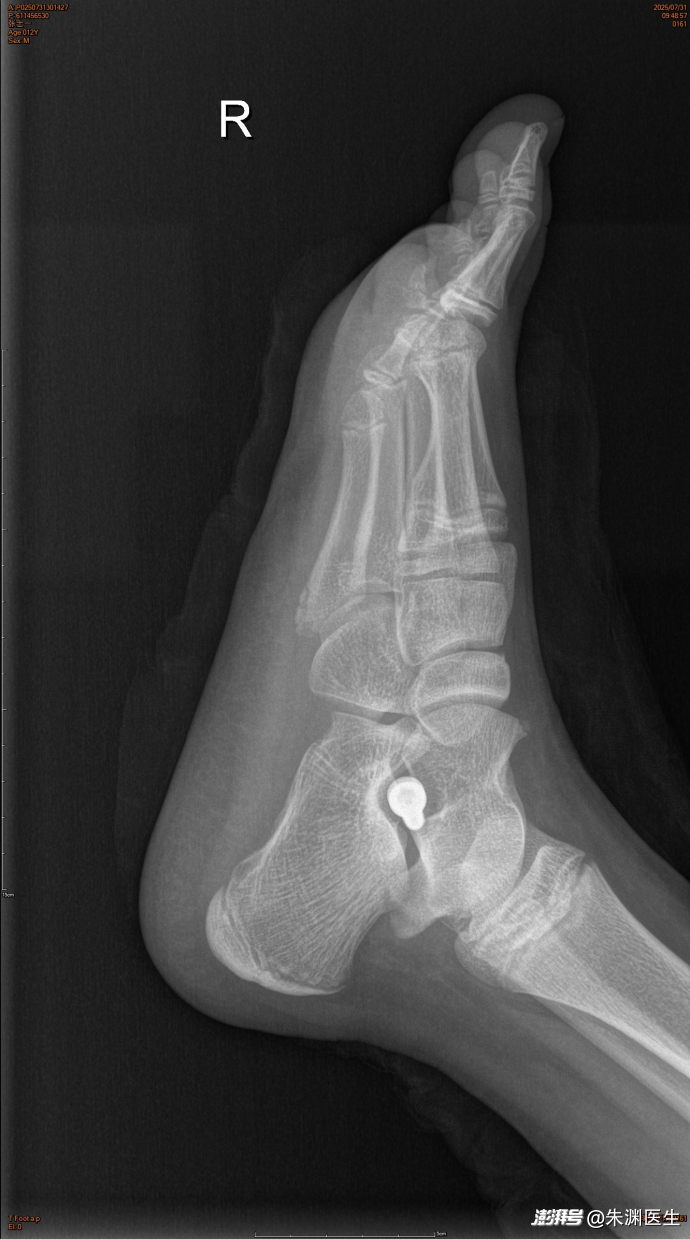

手术治疗青少年平足症。手术前外观、手术后可见骨缝里的金属内植物、术后外观和功能正常。